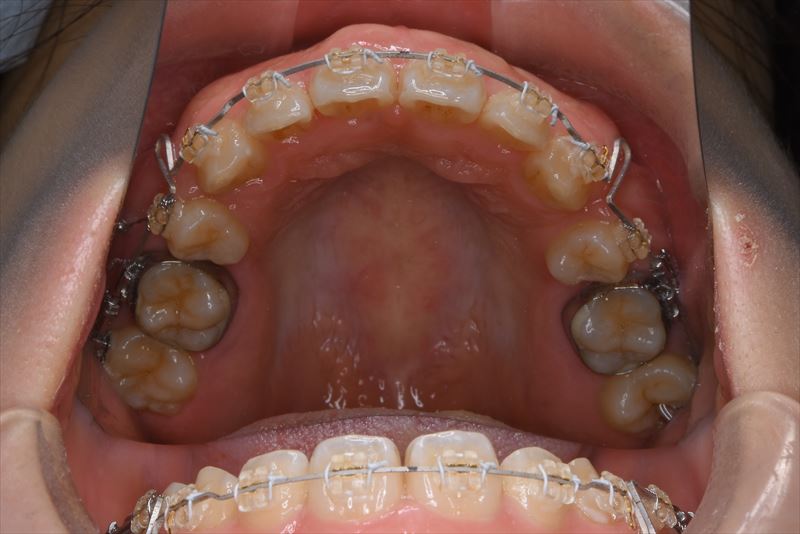

治療中

- 治療に用いた主な装置

- マルチブラケット装置、アンカースクリュー

- 上顎両側4番、下顎右側5番、下顎左側4番抜歯